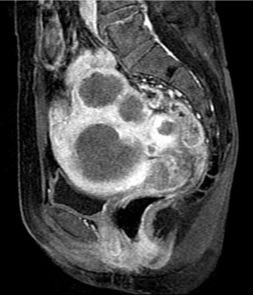

子宫肌瘤栓塞

| 术前 | 术后3个月 |

(expanded size 600-800) | 术前 | 术后 |